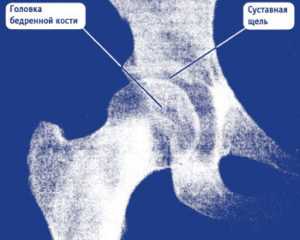

Снимок 1. На этом рентгеновском снимке изображен здоровый тазобедренный сустав. Мы можем здесь увидеть:

- правильную округлую форму головки бедренной кости;

- нормальных размеров суставную щель, т. е. достаточное расстояние между головкой бедренной кости и сочленяющейся с ней вертлужной впадиной.

Здоровый тазобедренный сустав. Фотография из архива доктора Евдокименко

Тем не менее этому пациенту почему-то поставили диагноз «коксартроз второй стадии» и приговорили к операции по замене сустава.

На самом деле никакого коксартроза у пациента не было и в помине. Да, он жаловался на боли в бедре, но эти боли были вызваны грыжей межпозвоночного диска и защемлением бедренного нерва (что впоследствии подтвердила томограмма позвоночника). Соответственно, операция по замене сустава пациенту была не нужна, а боли в бедре прошли после успешного лечения грыжи диска.